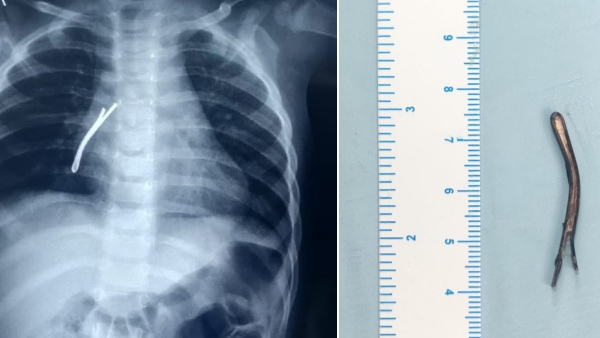

एम्स के डॉ विकास गुप्ता ने जानकारी देते हुए बताया कि हमने बच्चे की जांच के लिए ईएनटी सर्जनों की टीम बनाई। इसके बाद गहन जांच की गई। उसकी छाती की इमरजेंसी रेडियोग्राफी कराई गई। वही हाई रेगुलेशंस सीटी (कंप्यूटेड टोमोग्राफी) की गई। जिसकी रिपोर्ट सामने आने के बाद बच्चे के दाहिने फेफड़े यानी राइट ब्रोंकस की श्वास नली के निचले हिस्से में एक लंबा हेयर पिन फंसा दिखाई दिया।

4 सेंटीमीटर हेयर पिन को निकाला बाहर

इसके बाद टीम ने बच्ची को ऑपरेशन थिएटर के लिए रेडी किया गया। बच्ची को पहले सामान्य एनेस्थिसिया दी गई। इसकी मदद से बच्ची की आपातकालीन रिजिड ब्रोंकोस्कोपी की गई। बच्चे की दाहिनी तरफ श्वसन नली यानी ब्रोंकस से ऑप्टिकल चिमटे का उपयोग करते हुए हैरपीन को निकाला गया। यह हैरपीन करीब 4 सेंटीमीटर लंबी थी डॉक्टरों के मुताबिक श्वास नली में इस तरह की कोई भी भारी वस्तु फंस जाए तो वह जानलेवा हो सकती है।